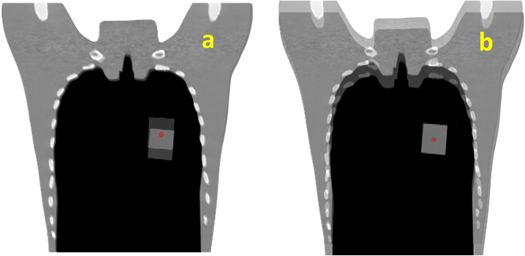

Standard image High-resolution imageBone matching (BM; figure 3(a)) and tumor matching (TM; figure 3(b)) are the two common methods of patient positioning correction adopted in clinical practice to determine the isocenter for irradiation of the day (Abe et al 2017). The dose distribution of the original treatment plan generated from the XiO-N® treatment planning system (Elekta Sweden; Mitsubishi Electric, Japan) was recalculated on the in-room and DVM CTs with different isocenters based on BM or TM to obtain the dose distributions for comparison. In addition, the dose distribution of the original plan was recalculated on the DVM CT with the isocenters calculated by the VOI and BV shifts to obtain the dose distribution of the DVM CT with the isocenter based on TM, which was DVM-TM, and that based on BM was DVM-BM. The dose distribution of the in-room CT with the isocenter based on TM was named InRoom-TM, and that on BM was InRoom-BM.

Figure 3. Illustration of bone matching (a) and tumor matching (b) for Scenario 1. The red dots represent the isocenter.

Download figure: